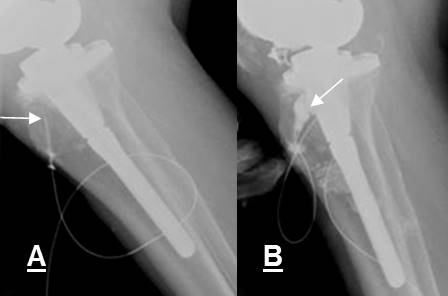

Fig 115. Mala posición del material.

A: Rx AP: Desplazamiento del tornillo de compresión, colocado en la cabeza femoral.

B: RM coronal en T1 y C: RM coronal en T2. Colección de tejidos blandos, hipointensa en T1 e hiperintensa en T2.